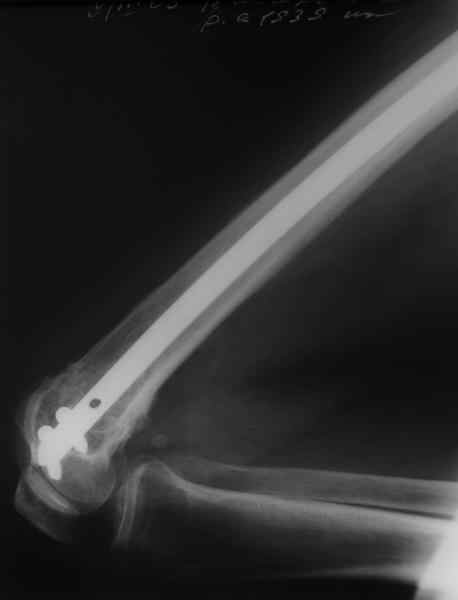

По прямой проекции неплохо. Что за стержень?

Антеградный остеосинтез при дистальных переломах бедра мы применяем давно, этот материал обобщен в канд. диссертации Александра Виноградского.

Примеры приложены.

Алекс, как Вы можете говорить, что "по прямой проекции неплохо"!? :( Гвоздь в суставе !!!

Снимаю свои претензии. На втором из снимков, которыми Вы хвастаетесь, гвоздь тоже в суставе, и ничего :(

И какие страшные проблемы от этого тянут аж на три восклицательных знака?

Если даже будет patellar impingement, это решается удалением после сращения.

Приносим извенения за недостаток информации. Выкладываю все снимки. Стержень фирмы НПО ДЕОСТ(г.Пущино-на-оке)

Чтобы больной не смог сгибать колено, выстоять в сустав железо должно побольше значительно, чем на 1 мм. В приложении снимок с выстоянием ммм на 3, видна и функция колена. Хотя клиника импинджмента была, но даже не на один восклицательный знак. После удаления стержня проблемы и вовсе рассосались.

Это результат через полгода. К сожалению, пациент больше не приезжал на контрольный осмотр.